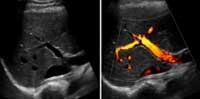

A Doppler ultrasound study may be part of an abdominal ultrasound examination.

Doppler ultrasound is a special ultrasound technique that evaluates blood flow through a blood vessel, including the body's major arteries and veins in the abdomen, arms, legs and neck.

Doppler ultrasound, a special application of ultrasound, measures the direction and speed of blood cells as they move through vessels. The movement of blood cells causes a change in pitch of the reflected sound waves (called the Doppler Effect). A computer collects and processes the sounds and creates graphs or color pictures that represent the flow of blood through the blood vessels.